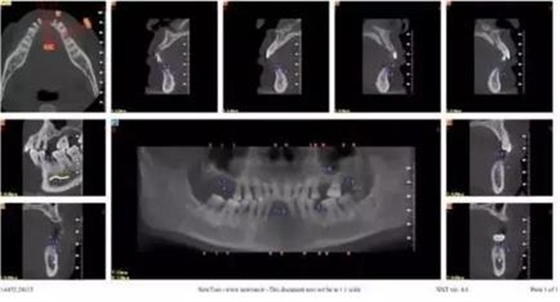

拔牙前CT截圖

以修復(fù)為導(dǎo)向規(guī)劃植體

牙支持式導(dǎo)板生成